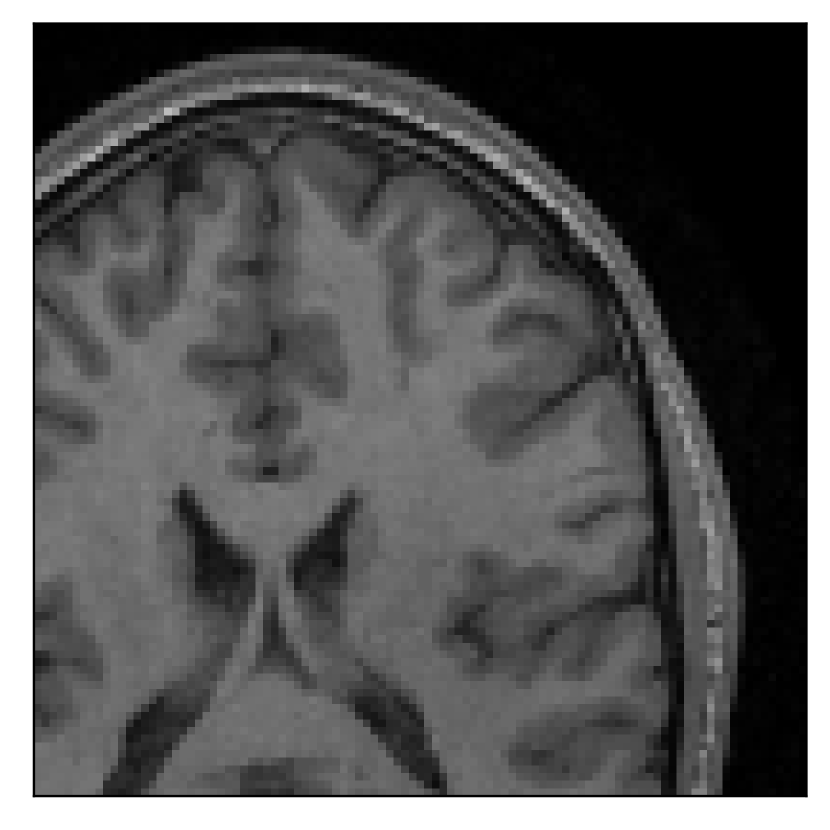

3.2 Experiment 2: on the choice of the reference contrast

This in-vivo experiment tests the proposed correction scheme with respect to a different combination of corrupted and reference contrast, namely a T1-weighted corrupted contrast with a T2-weighted reference contrast (see Table 1). For this experiment, we prompt volunteer 2 to move five times during the acquisition. The corrupted acquisition employs randomized sampling.

In Section 4.2, we gather the results for this experiment.

| Section 3.2, Figure 10 | Sagittal | 25.84 | 28.07 | 0.7032 | 0.8093 |

| Coronal | 26.35 | 30.40 | 0.7851 | 0.9021 | |

| Axial | 28.11 | 30.54 | 0.8248 | 0.9012 | |

The motion-corrected full-volume scans were analyzed by a neuroradiologist with 16 years of experience. These were generally deemed of good radiological quality. The motion-related artifacts have been completely removed, and the results are quite close to the ground truth. In Table 3, we organized a more detailed qualitative analysis of the 3D results, geared toward a radiological assessment of the corrected scans.

| Section 3.2, Figure 10 | T1 | Completely corrected | Some blurring | No additional artifacts | Good grey white matter differentiation, |

| some loss of grey matter low signal | |||||

4.2 Experiment 2: choice of the reference contrast

With the experiment described in Section 3.2, we demonstrate the flexibility of the correction scheme with respect to the choice of the reference contrast. The results are shown in Figure 10. Contrary to the experiments detailed in the previous section, we are now considering a T2-weighted reference contrast to guide the correction of a T1-weighted corrupted contrast. The quality of the correction indicates that the proposed technique is rather flexible in terms of reference contrast.